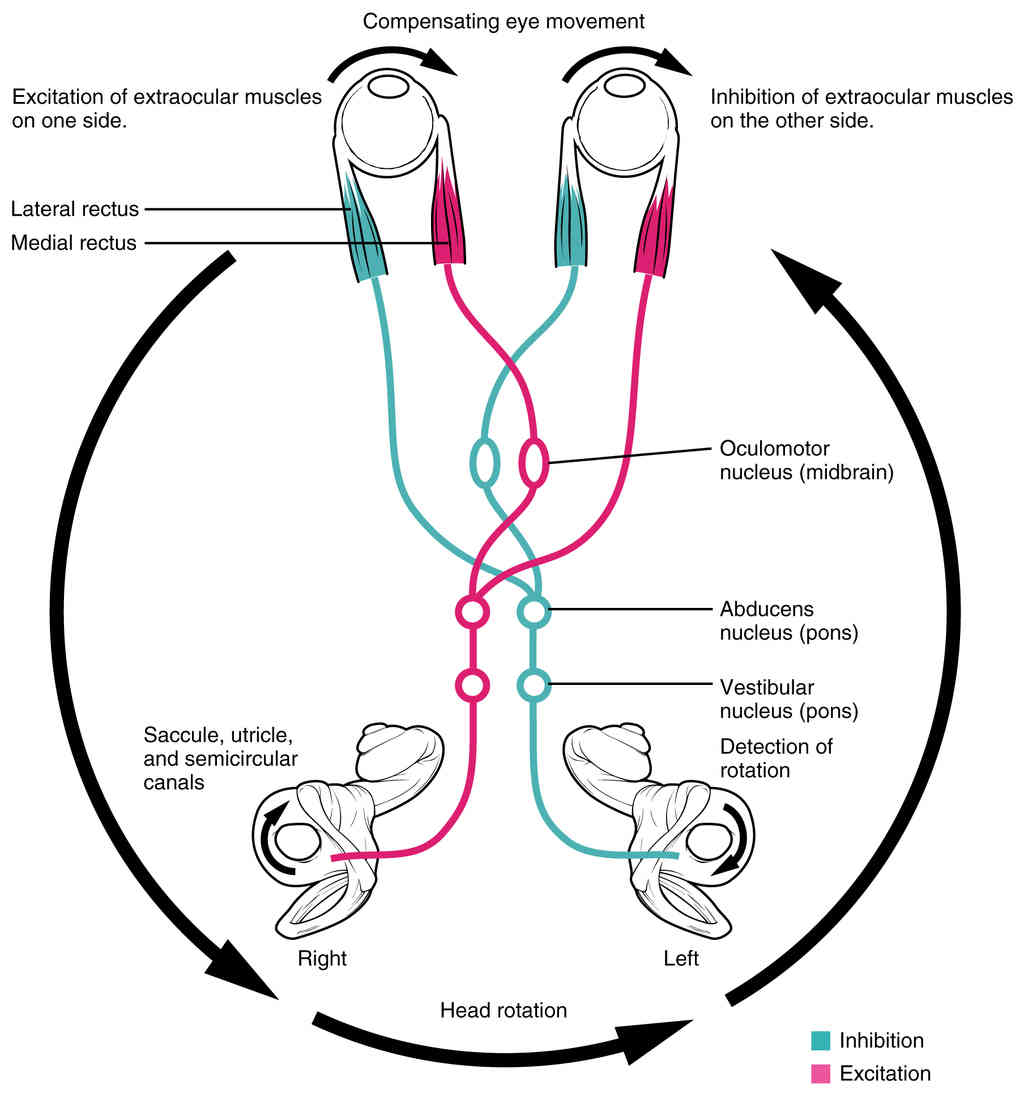

This page is under construction. For now, it is just a resource of the images found in the OpenStax Anatomy and Physiology Handbook. It wil slowly change into a revision tool. Each slide has a number. Use this to refer to the slide. When completed, it will have an unlabelled section, with labelled slides in parallel. On the unlabelled slides, write your answer and use the labelled slide to assess yourself. Keep track by also noting the number on each slide. Improvement at each attempt is important, more so than full marks on a first attempt.